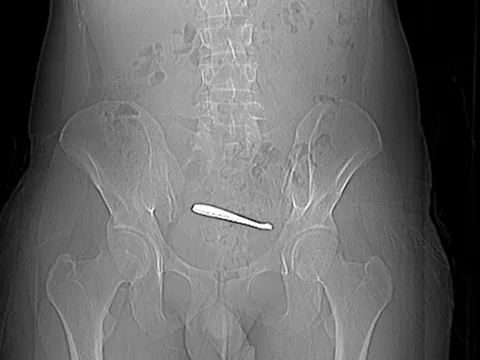

Nguy kịch vì triền miên quá chén - Ảnh 1.

Nhiều người nhập viện vì viêm tụy cấp